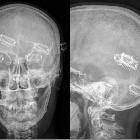

Haarverlängerungen

mit Clips im seitlichen Röntgenbild des Schädels

Artificial

hair extensions in X-ray.

Hair-Clip-Extensions

im Röntgenbild